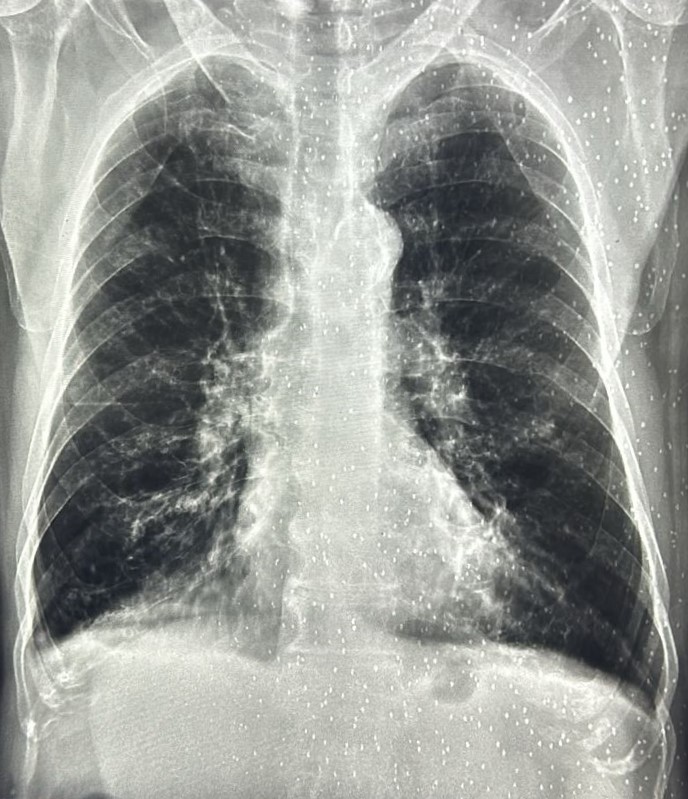

| 332 | IGGMC, Nagpur, Nagpur | P2 | 29-4140 | Mohamad Bashir | Consent taken on Paper | 75 Yrs. |

Provisional Diag : COPD

Final Diag : COPD In intense exerbation |

Non-TB Case (Confirmed) | COPD changes seen | Abnormality visible on x-ray |